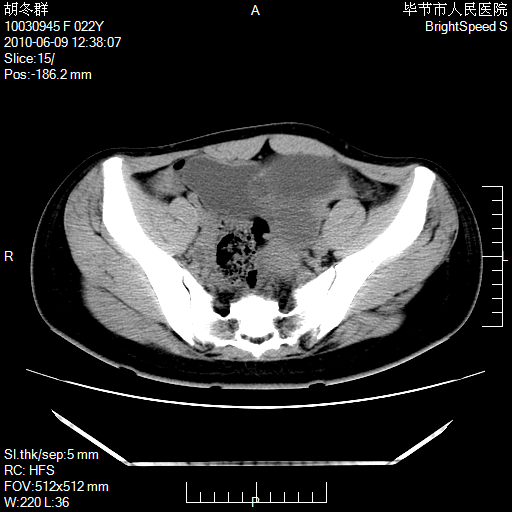

患者23岁,发现腹部包块3月。

盆腔内囊性占位;穿刺或者直接手术拿掉即可,不必紧张。

囊性病变,可以增强检查,不除外输尿管囊肿

盆腔内囊性占位性病变;考虑左侧卵巢囊腺瘤。

有分隔、壁薄,支持考虑左侧卵巢囊腺瘤。

左侧卵巢浆液性囊腺瘤。

有分隔、壁薄,支持考虑左侧卵巢囊腺瘤。排尿后,膀胱缩小,由于重力作用,肿块下移就到了膀胱位置,很好理解。